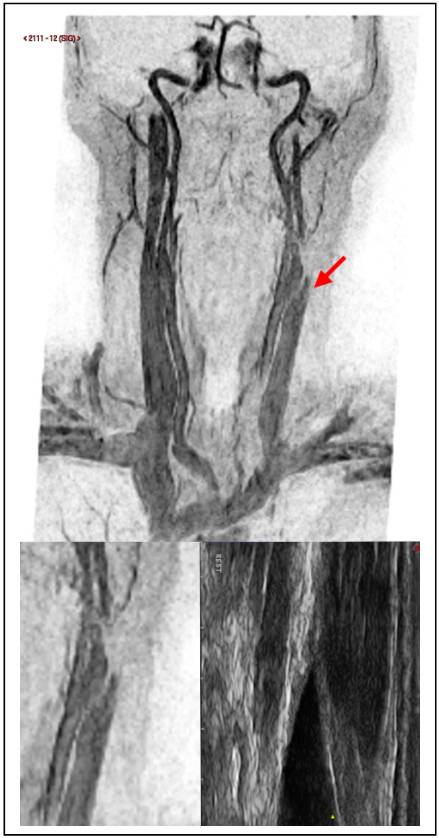

At 1 year follow up the EDSS was 3 again and the patient reported recurrent fatigue that she had been experiencing for several months. Further investigation revealed a CCSVI related left IJV tandem obstruction. At mid cervical level B-mode color Doppler demonstrated an IJV obstruction mirrored by an MRV imaging. In both cases a pencil tip pencil sign was demonstrated (Figure 2). The color Doppler assessment highlighted a left IJV dynamic flow obstacle caused by an extrinsic compression (Figure 2), that could be relieved by yawning.